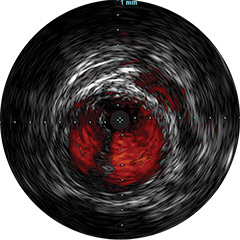

Digital IVUS imaging

imaging

imaging

imaging

Orientación IVUS

es "definitivamente beneficiosa" para los pacientes, y dio lugar a un cambio de los planes de tratamiento el 74% de las veces 1,6,7

Figura 3

Figura 4